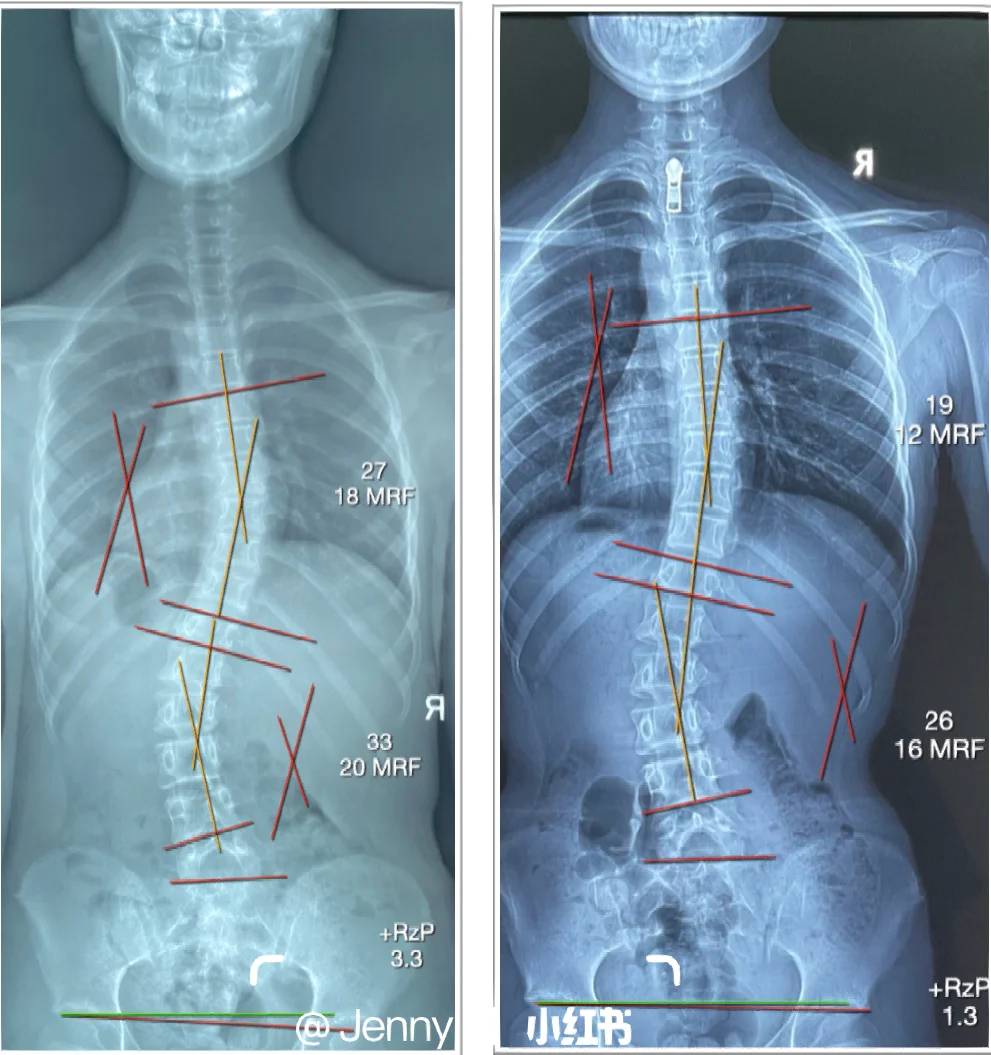

脊柱侧弯的矫正需根据侧弯程度病因及人群特点制定个体化方案,主要分为非手术矫正和手术矫正两类一观察评估是矫正的前提首先需通过脊柱X线检查明确侧弯角度Cobb角小于20°为轻度,20°40°为中度,大于40°为重度同时需鉴别病因,如特发性最常见,多见于青少年先天性胚胎发育异常。

脊柱侧弯的矫正需根据侧弯度数及个体情况选择合适方法,具体如下一轻度侧弯20度以下观察与习惯调整若侧弯角度小于20度,通常无需特殊治疗,但需定期监测如每6个月复查X光,观察角度变化日常需避免久站久坐或长时间保持同一姿势,每30分钟活动身体,保持脊柱自然生理曲度同时,加强核心。